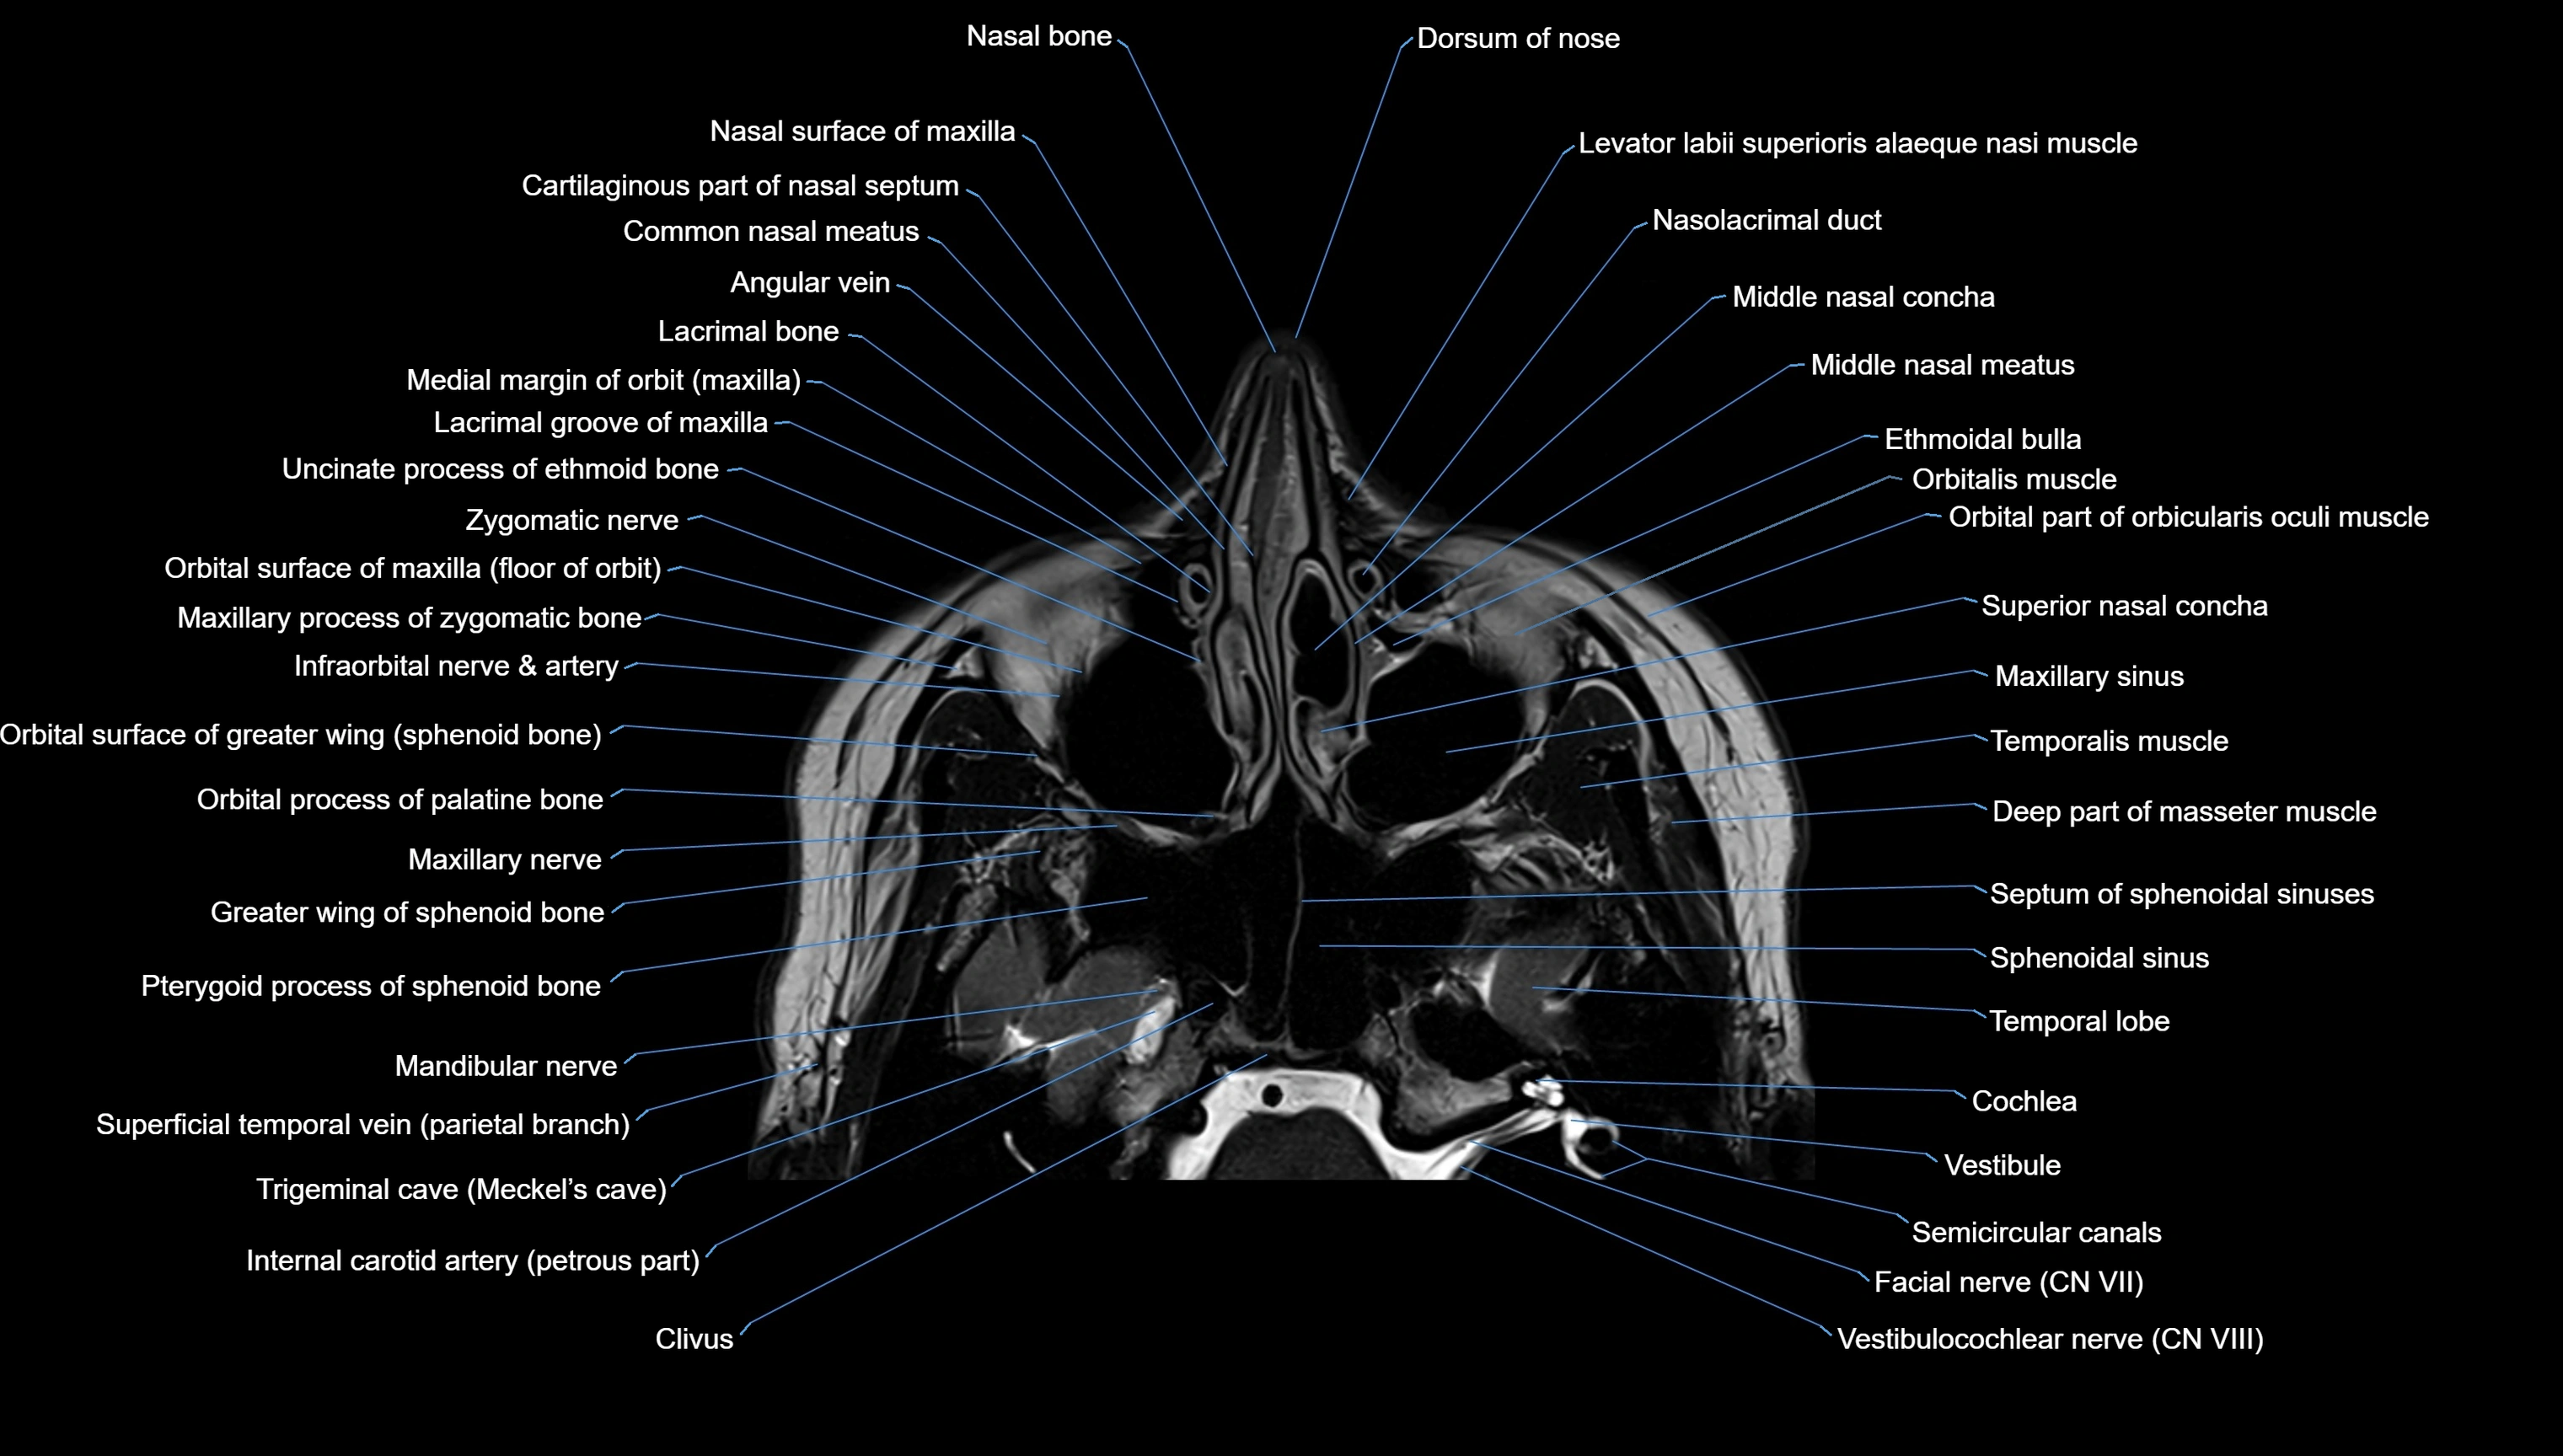

- Dorsum of nose

- Cartilaginous part of nasal septum

- Common nasal meatus

- Lacrimal bone

- Middle nasal concha

- Middle Nasal Meatus

- Maxillary sinus

- Sphenoidal sinus

- Cochlea

- Semicircular Canals

- Vestibule

- Vestibulocochlear nerve (Cranial nerve VIII)

- Facial Nerve (Cranial nerve VII)

- Zygomatic nerve

- Mandibular nerve

- Maxillary nerve

- Clivus